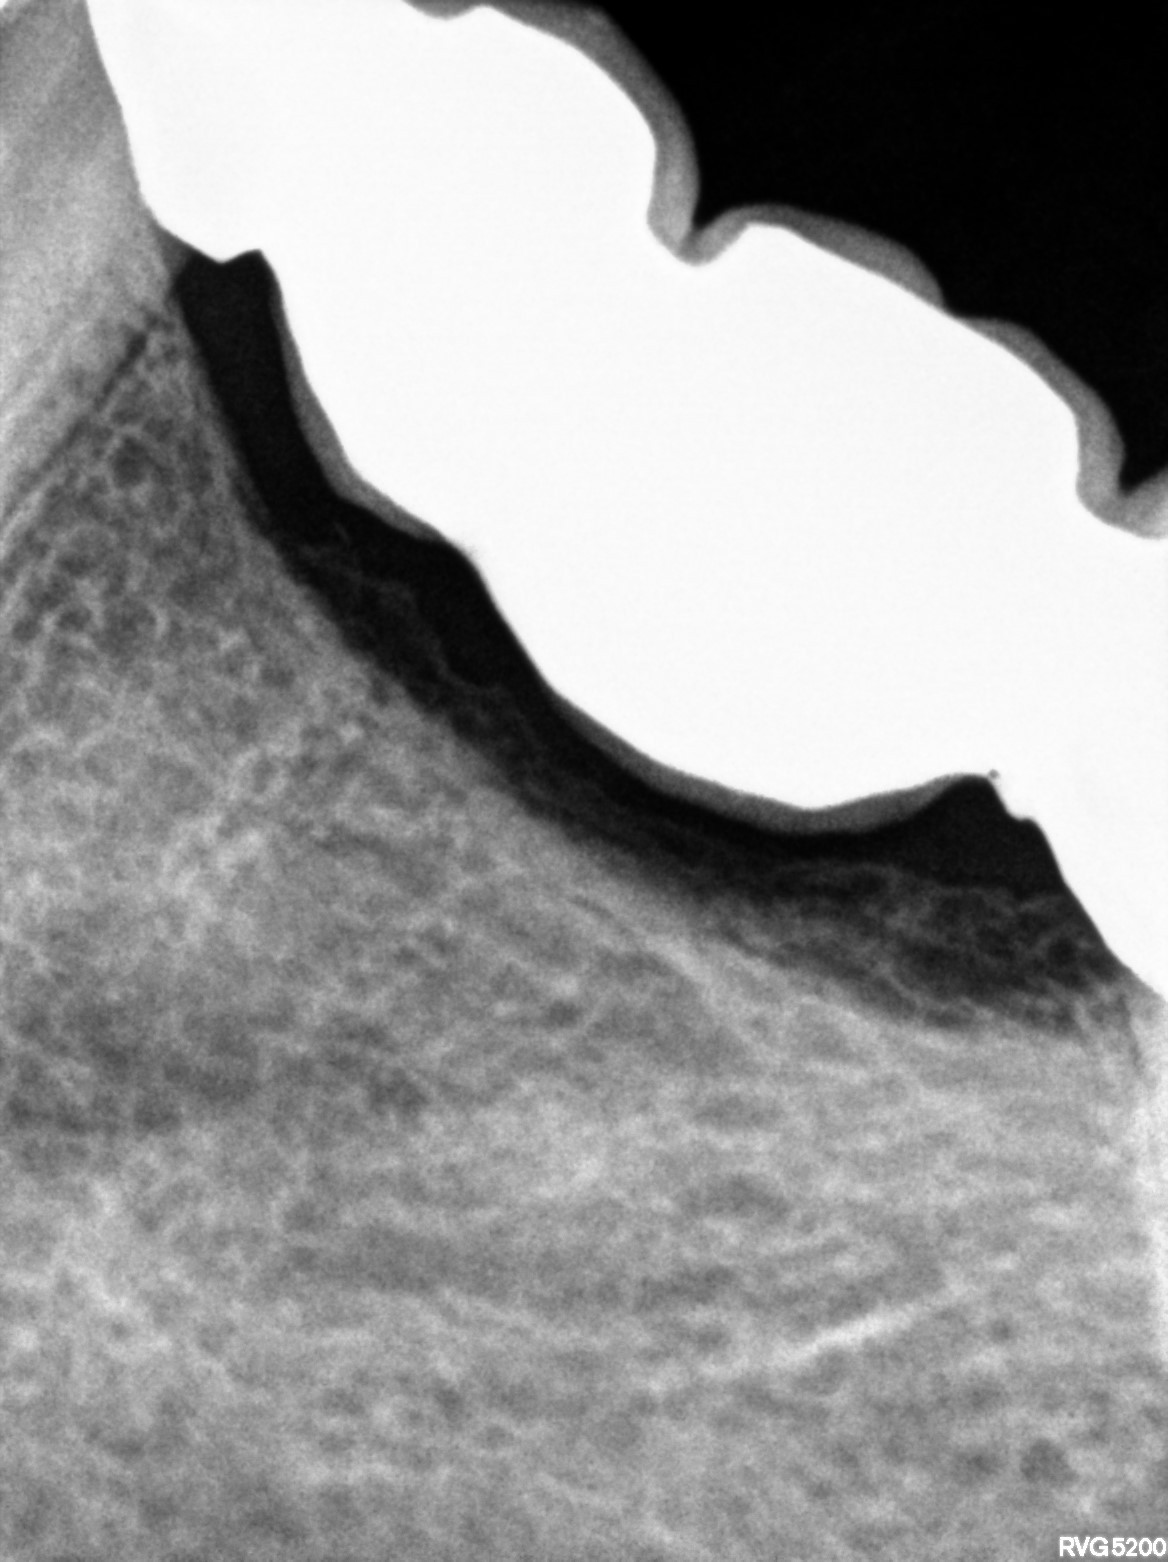

Dental Radiographs FHIR: DocumentReference · LOINC 24641-7

xray_1763362538_0.jpg

24641-7